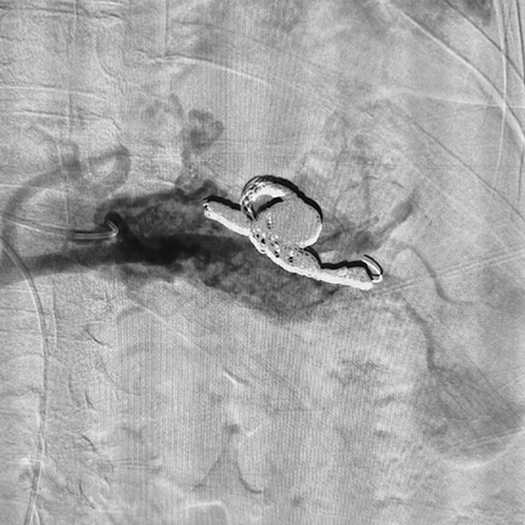

Ruby® Coil Dr. Eduardo Bent Robinson UCHealth University of Colorado Hospital, CO